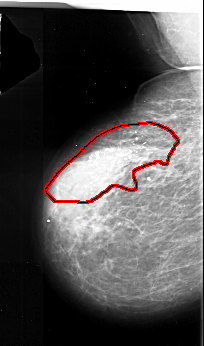

A_1017_1.LEFT_CC

LEFT_CC LINES 5221 PIXELS_PER_LINE 3586 BITS_PER_PIXEL 16 RESOLUTION 42 OVERLAY

FILE: A_1017_1.LEFT_CC.OVERLAY

TOTAL_ABNORMALITIES 1

ABNORMALITY 1

LESION_TYPE CALCIFICATION TYPE PLEOMORPHIC DISTRIBUTION SEGMENTAL

ASSESSMENT 5

SUBTLETY 5

PATHOLOGY MALIGNANT

TOTAL_OUTLINES 1

BOUNDARY